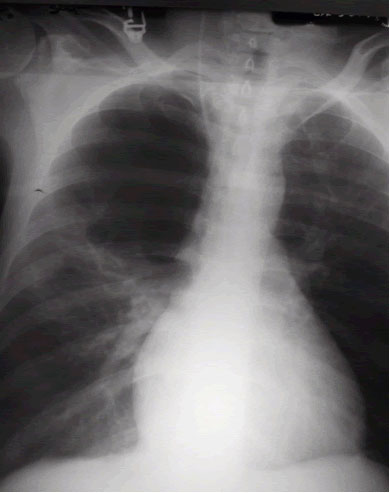

Bullous lung disease symptoms. There are several subtypes of emphysema including subcutaneous emphysema bullous. Group B GOLD 1 or 2. Most people with bullous emphysema experience shortness of breath wheezing coughing up phlegm and centralized pain in their chests especially when engaging in physical activity.

This emphysema also includes deterioration of alveolar tissue and this is basically lung tissue that makes up the walls between air sacs. Bullous Lung Disease is the most common form of emphysema. As the disease gets worse scars form and the tissue becomes stiff and thick.

Some patients suffer from nausea loss of appetite and fatigue as a. Patients frequently present with nonspecific symptoms including intermittent wheeze and cough and these are often attributed to other conditions such as asthma and smoking-related COPD especially when there is concurrent heavy smoking history. As the disease progresses you may find it increasingly difficult to breathe and engage in daily activity.

Emphysematous bullae can cause many respiratory problems including shortness of breath. Your FEV 1 is between 50 and 80. The harmful effects of tobacco smoking especially with regard to the aetiology of chronic obstructive pulmonary disease are well documented3 Large emphysematous bullae may develop usually in the context of significant tobacco exposure over many years and tend to be associated with airway obstruction reduced gas transfer factor and diffusion coefficient and evidence of centrilobular.

This is condition which is characterized by abnormal and enlarged air spaces within the lungs.